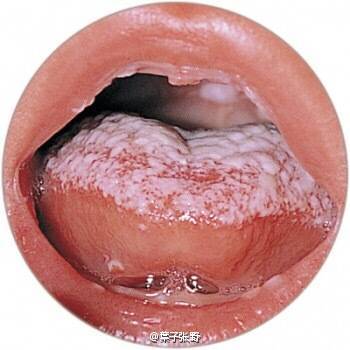

宝宝嘴巴长鹅口疮图片_有来医生

图片尺寸860x1152

鹅口疮转载

图片尺寸350x350